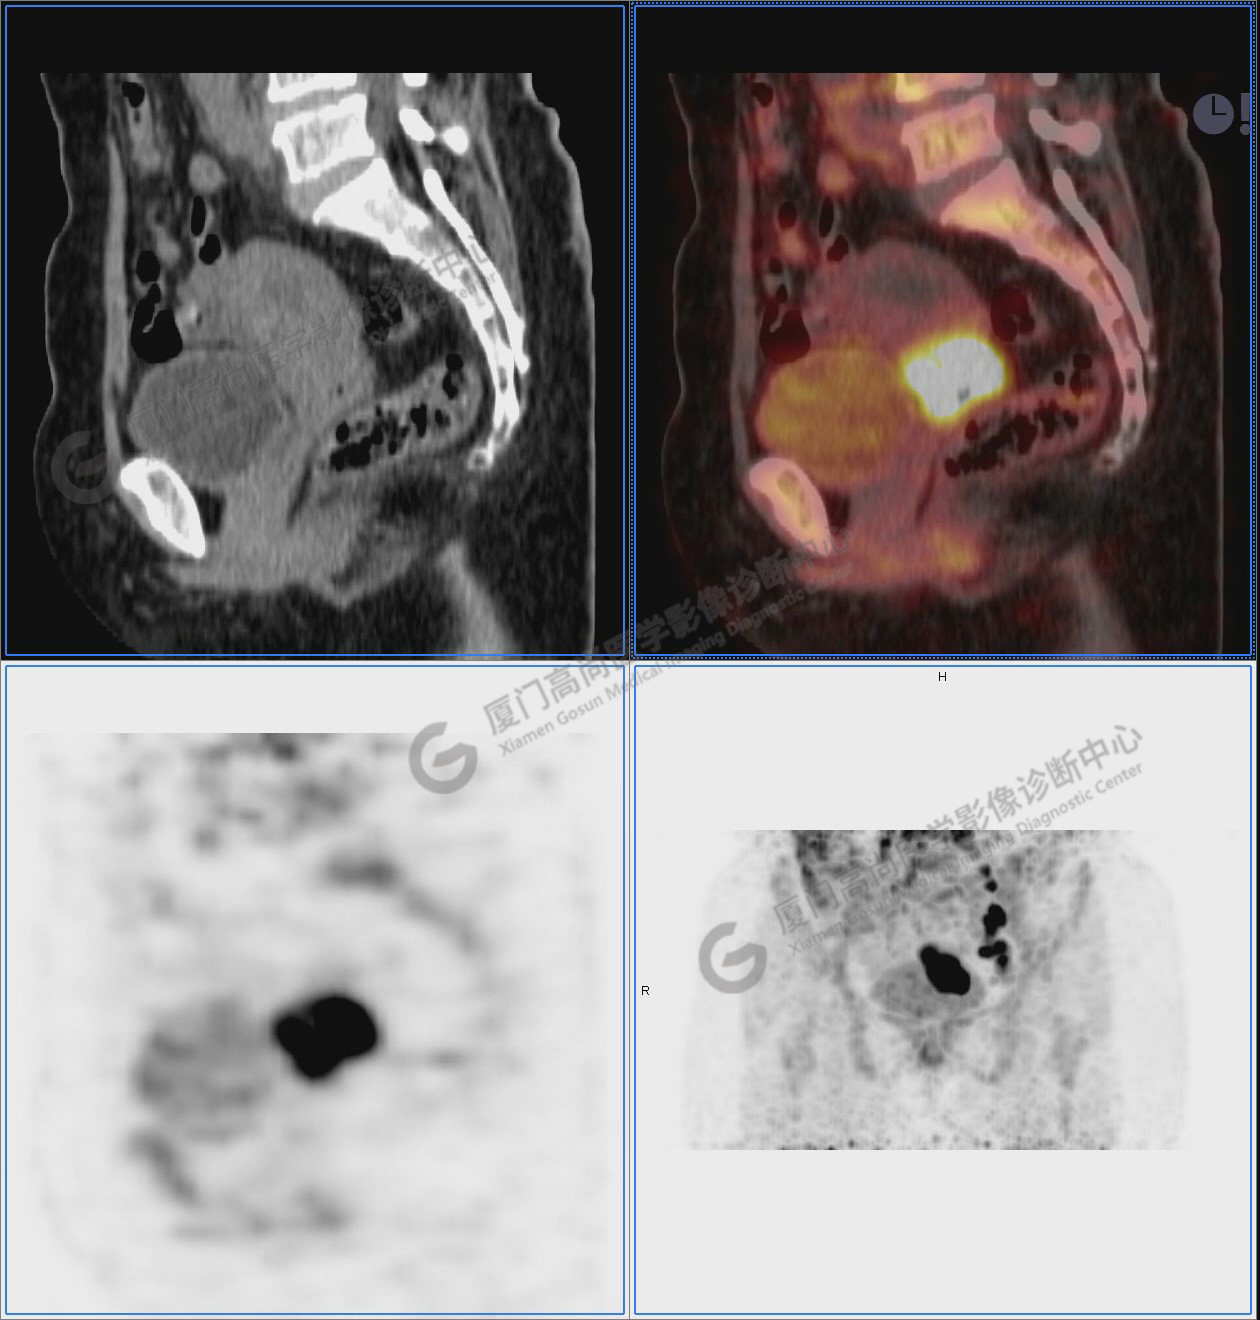

圖2-9:雙側(cè)鎖骨區(qū)、縱隔、右側(cè)內(nèi)乳區(qū)、腸系膜緣、腹膜后、雙側(cè)髂血管旁及盆腔多發(fā)腫大淋巴結(jié)影,代謝不同程度增高,考慮為轉(zhuǎn)移。

圖10-11:子宮頸軟組織腫塊,代謝異常增高,考慮為宮頸癌。

圖12-13:延遲2小時后,宮頸腫塊糖代謝進一步增高。